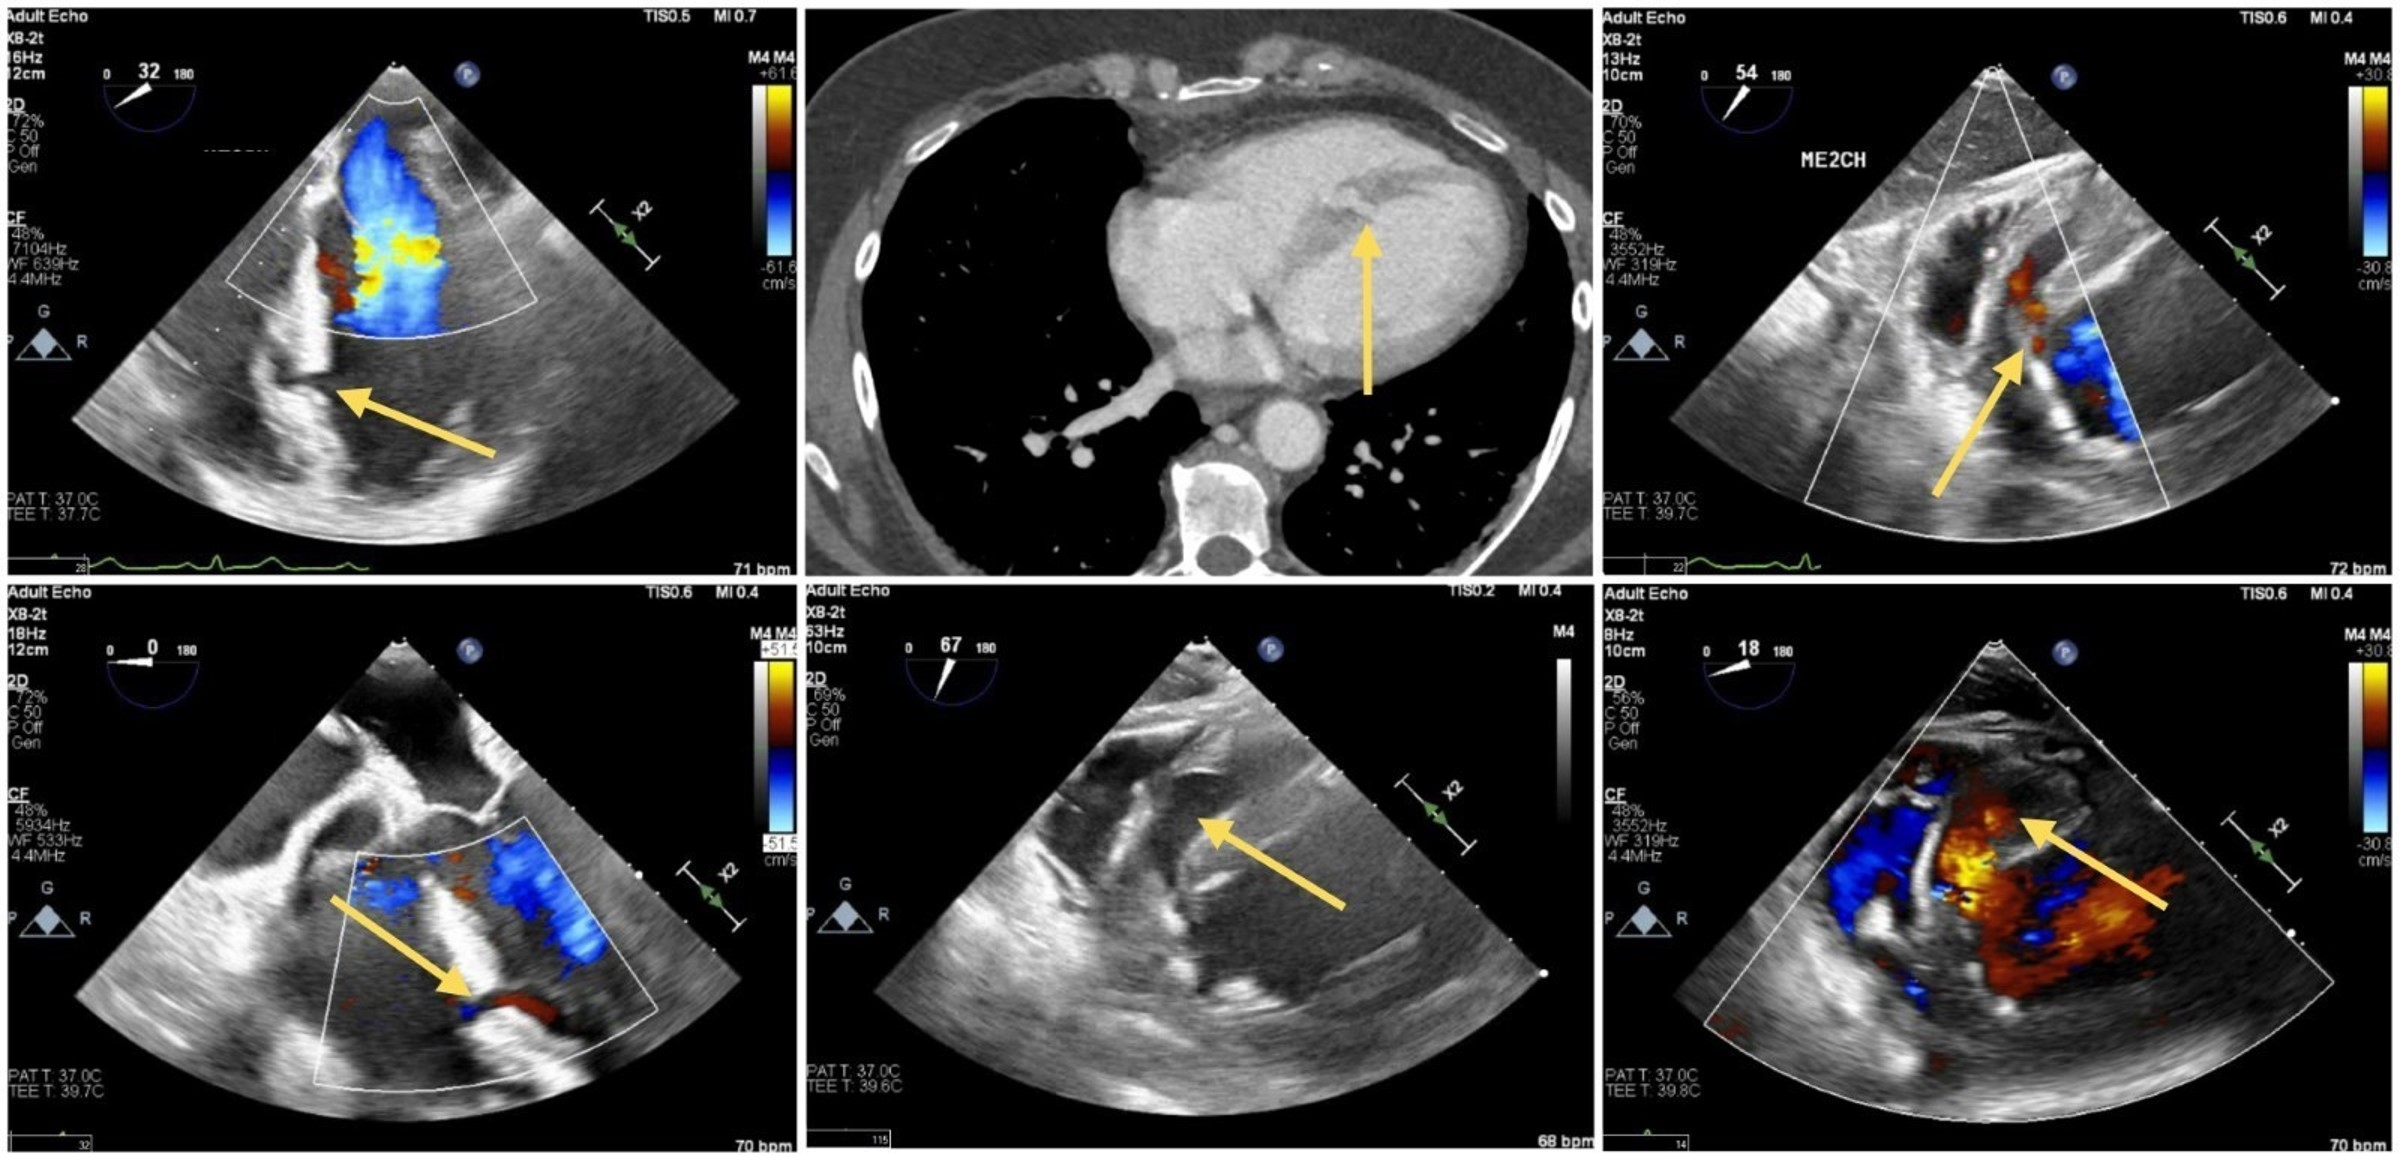

A healthy 55-year-old female presented after blunt chest trauma from a car accident. Bedside echocardiogram revealed a mid-septal LV discontinuity with myocardial outpouching. Lab work was significant for high sensitivity troponin of 22,000 ng/L which peaked at 24,000 in 5 hours. ECG revealed normal sinus rhythm with a QRS duration of 102ms. No ventricular ectopy was detected. Transthoracic echocardiograph (TTE) using echo contrast agent and computed tomography (CT) scan confirmed the intraventricular pseudoaneurysm (Fig 1-A&B).

A transesophageal echocardiogram (TEE) showed an intact PSA at 3.7 x 2.5 cm LV PSA with a 5mm neck extending from the mid septum superiorly into the right ventricle (RV) with no Doppler evidence of rupture or shunt (Fig 2). With cardiology and cardiac surgery shared decision making, conservative therapy was elected in the setting of polytrauma and hemodynamic stability. Serial TTEs showed stable size and appearance of the PSA during her month long hospitalization.

LV septal PSA is rare following blunt chest trauma, and it confers a considerable risk of rupture with the highest risk occurring within 3 months of formation. Untreated PSA presents with risks including thromboembolism, infection, and arrhythmia. Multimodal cardiac imaging is paramount for diagnosis and surveillance. There are no guidelines for serial monitoring in hemodynamically stable patients and an individualized approach should be taken. In this patient TTE, TEE, and CT imaging modalities were utilized. Our patient progressed without complication following conservative management with shrinking and scarring of the aneurysm characterized by the cMRI.